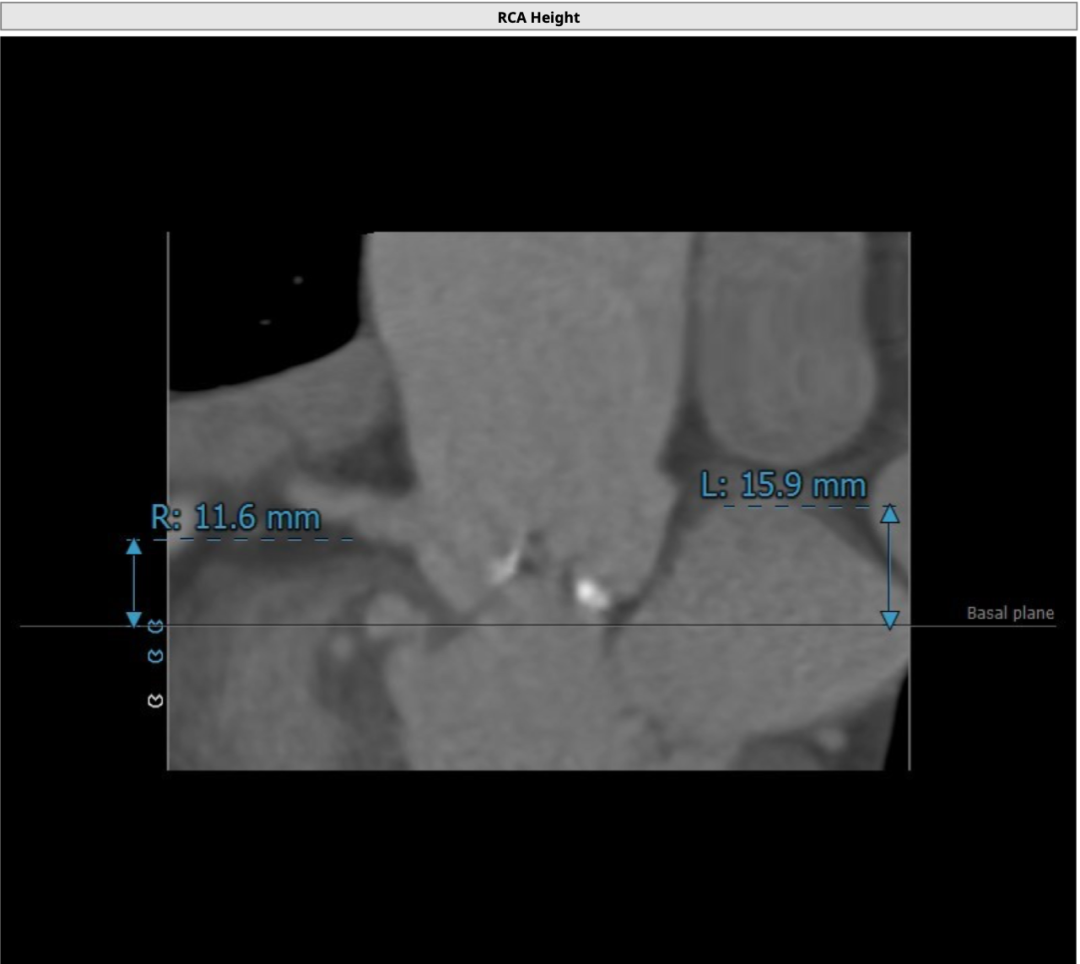

11.png

右冠开口

该名患者为Type 0型二叶瓣,钙化分布不对称,瓣叶有轻度增厚。瓣环最短径为19.6mm,最长径为25.2mm,平均瓣环直径为22.4mm。左冠开口高度15.6mm,右冠开口高度15.9mm。